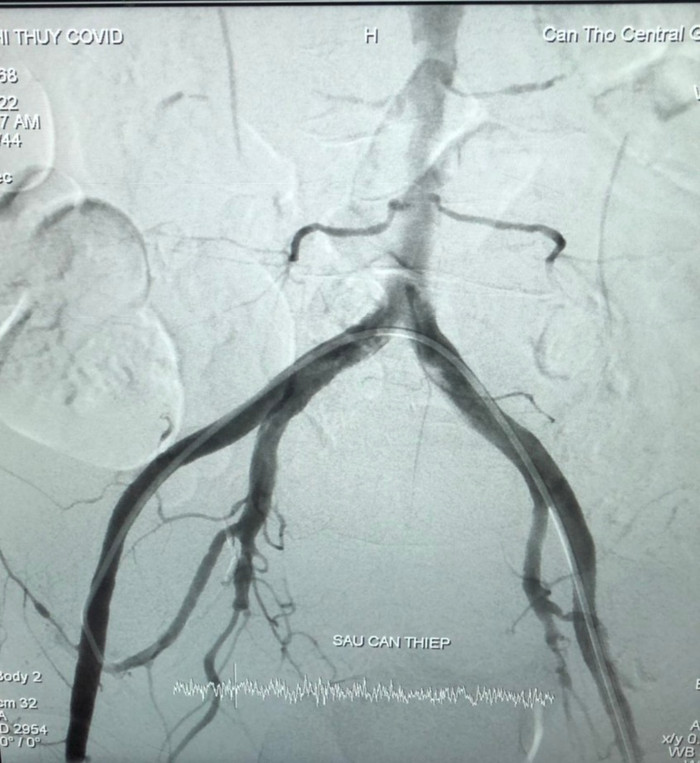

Kỹ thuật thành công sau 60 phút, ổ xuất huyết đã được kiểm soát, tắc hoàn toàn. Tình trạng bệnh nhân sau can thiệp huyết động và toàn trạng ổn định dần. Bệnh nhân xét nghiệm Covid-19 bằng kỹ thuật RT- PCR cho kết quả âm tính nên được chuyển đến khoa Nội Hô hấp điều trị.

Hình ảnh sau can thiệp.